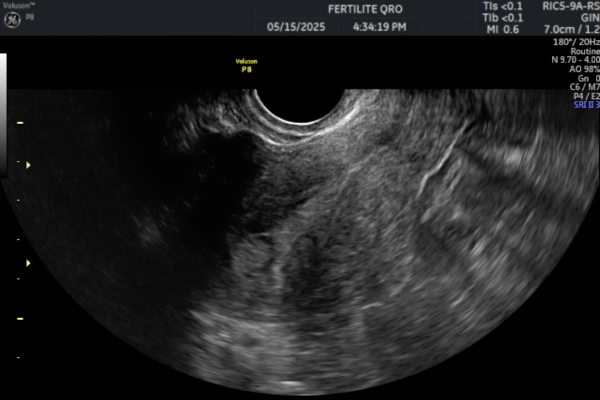

Imágenes de pólipos endometriales

- Ecografía transvaginal:

Es el primer estudio recomendado. Permite observar engrosamientos o imágenes compatibles con pólipos dentro del endometrio. Es rápida, accesible y no invasiva.